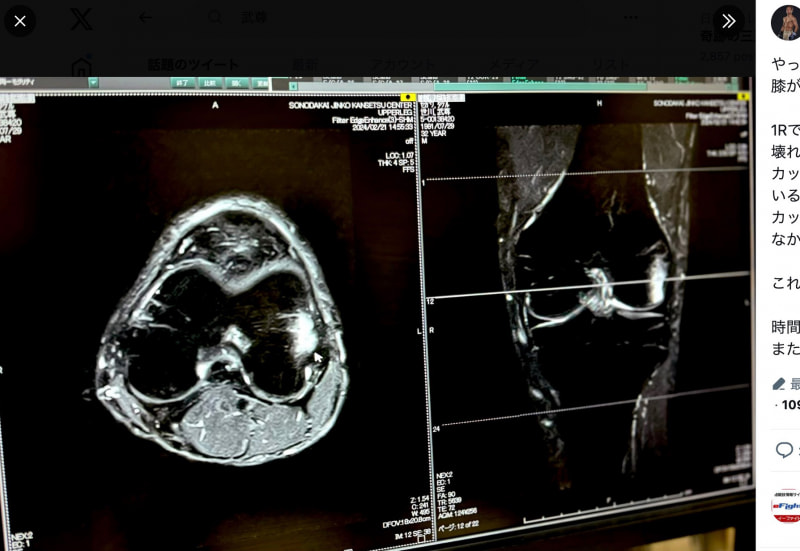

武尊が公開したレントゲン写真、ヒザの2箇所骨折を報告(@takerusegawa)